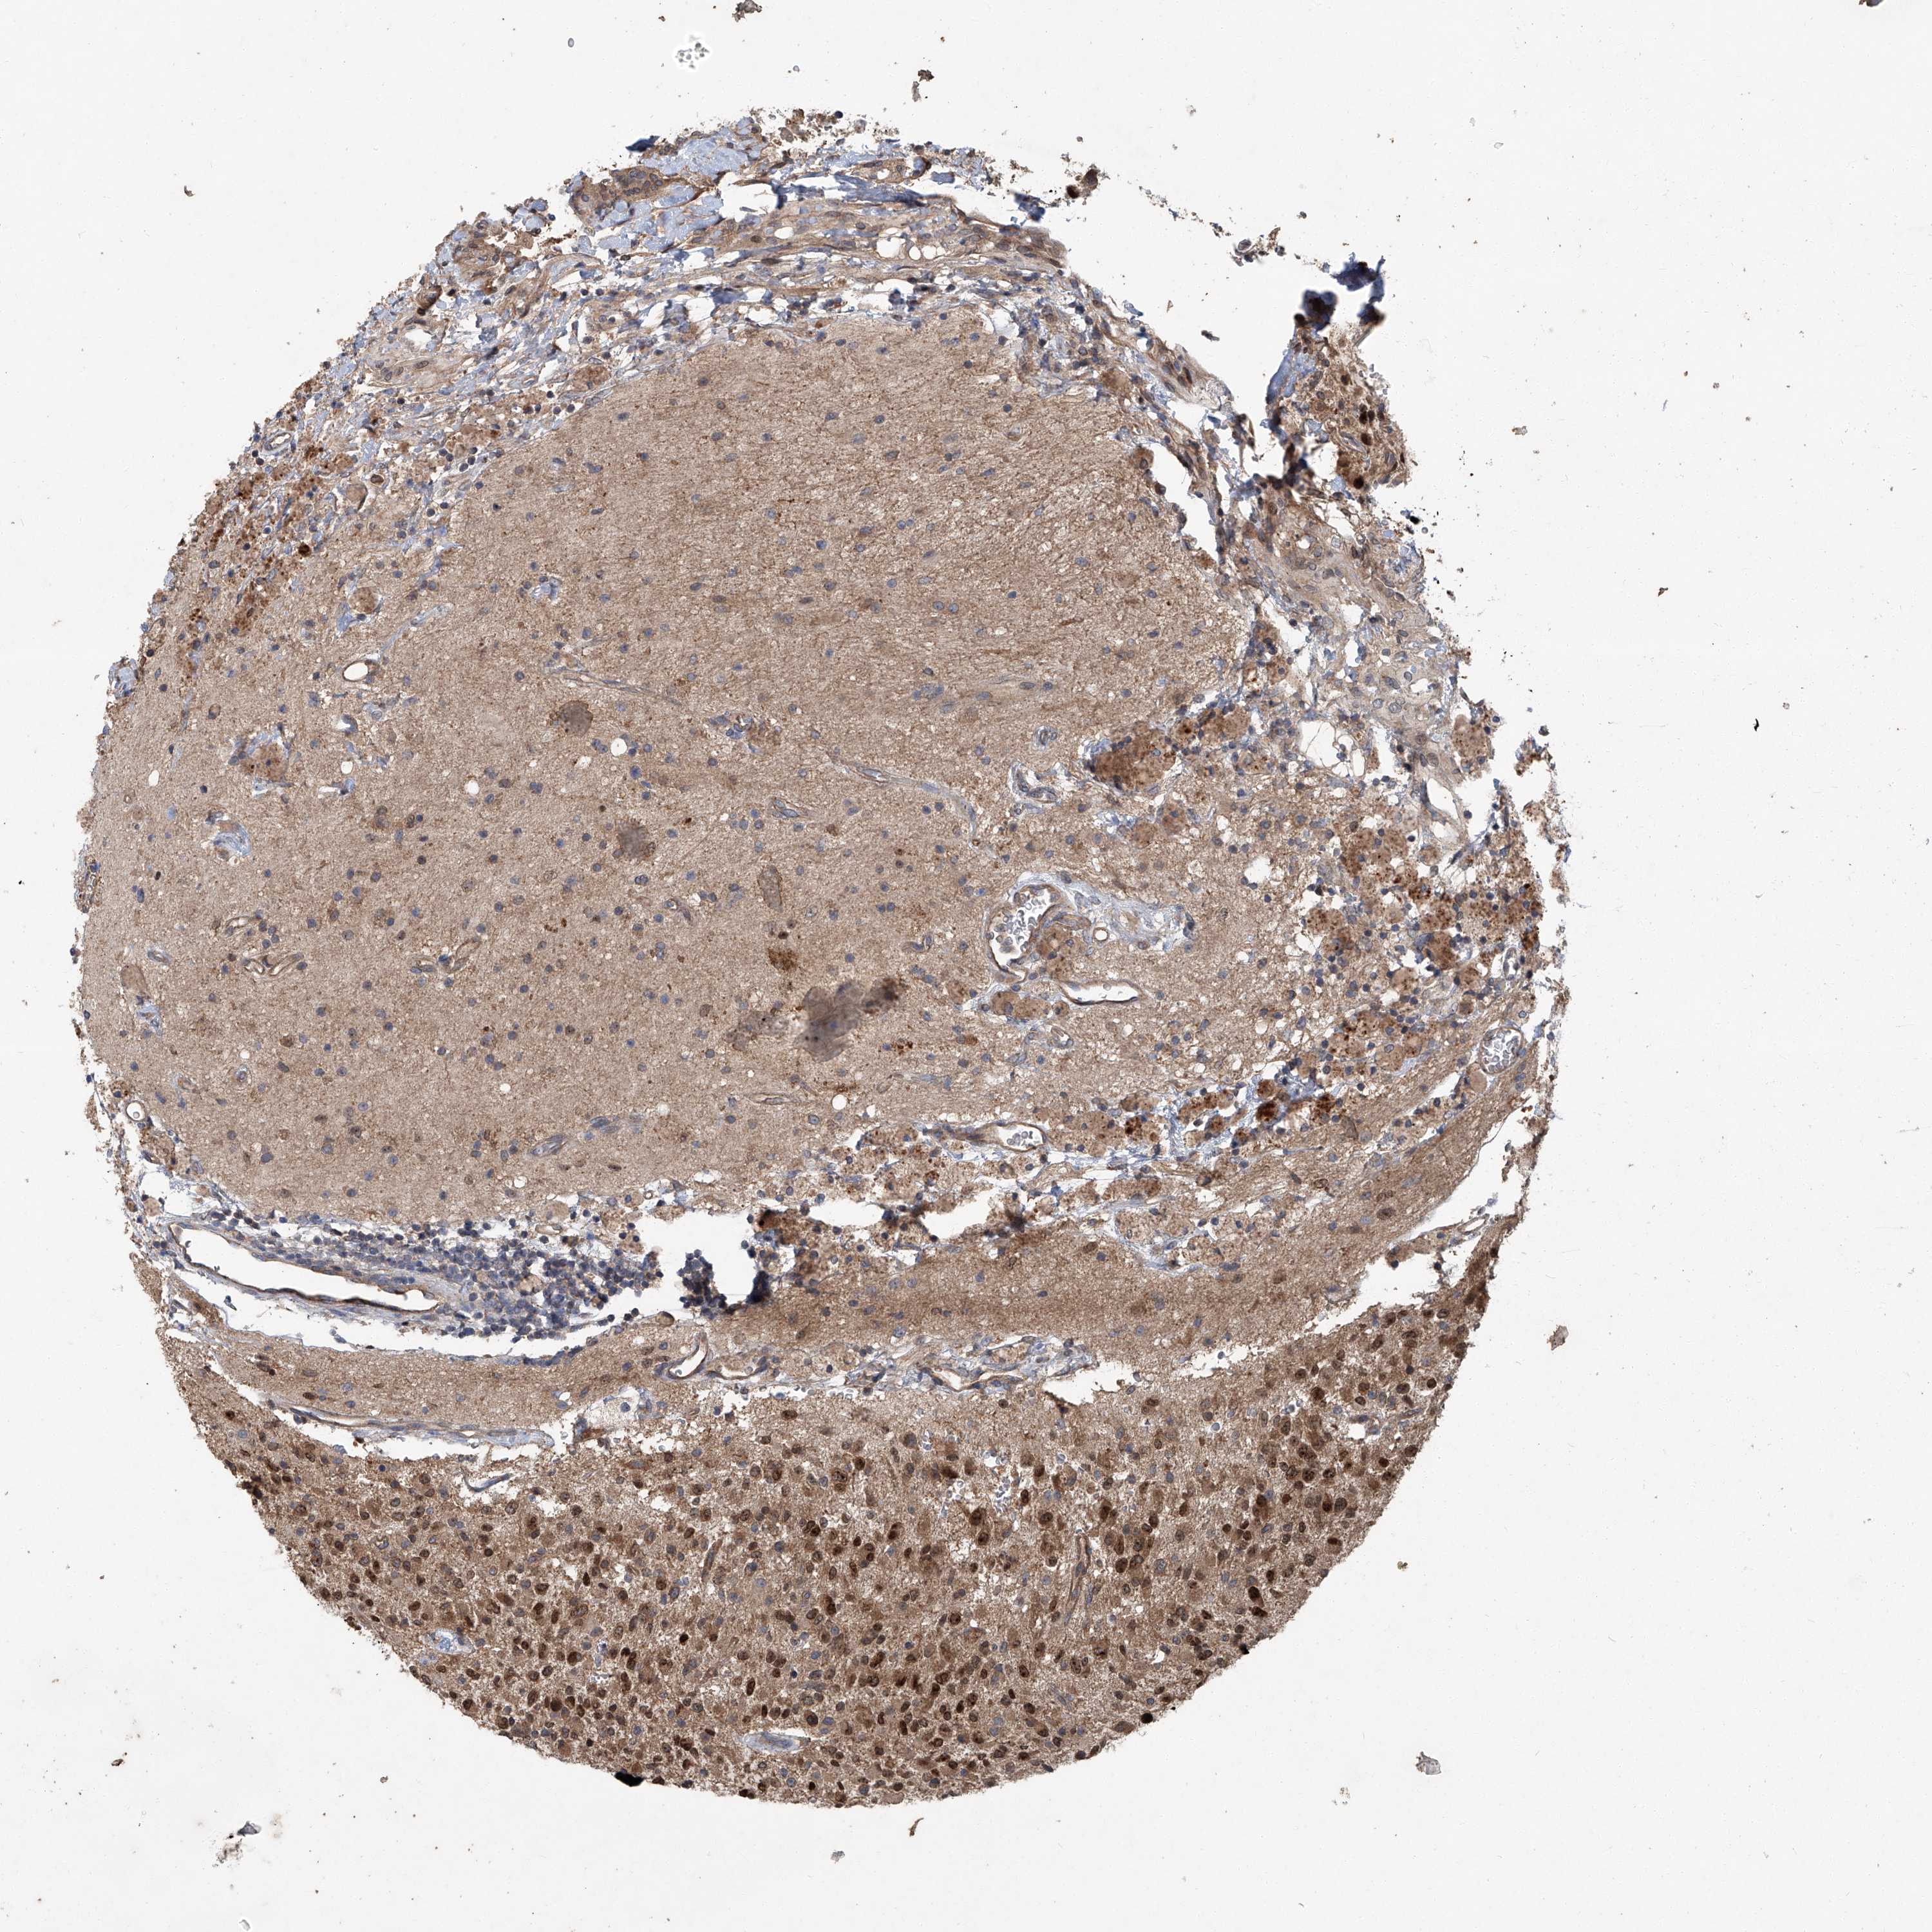

GLIOMA - Protein expressioni

A mouse-over function shows sample information and annotation data. Click on an image to view it in a full screen mode. Samples can be filtered based on level of antibody staining by selecting one or several of the following categories: high, medium, low and not detected. The assay and annotation is described here.

Note that samples used for immunohistochemistry by the Human Protein Atlas do not correspond to samples in the TCGA dataset.

Antibody stainingi

Antibody staining in the annotated cell types in the current human tissue is reported as not detected, low, medium, or high, based on conventional immunohistochemistry profiling in selected tissues. This score is based on the combination of the staining intensity and fraction of stained cells.

Each image is clickable and will lead to virtual microscopy that enables deeper exploration of all samples and also displays staining intensity scores, fraction scores and subcellular localization as well as patient and tissue information for each sample.

Antibody HPA029642

Antibody HPA029643

Glioma, malignant, High grade

Glioma, malignant, Low grade